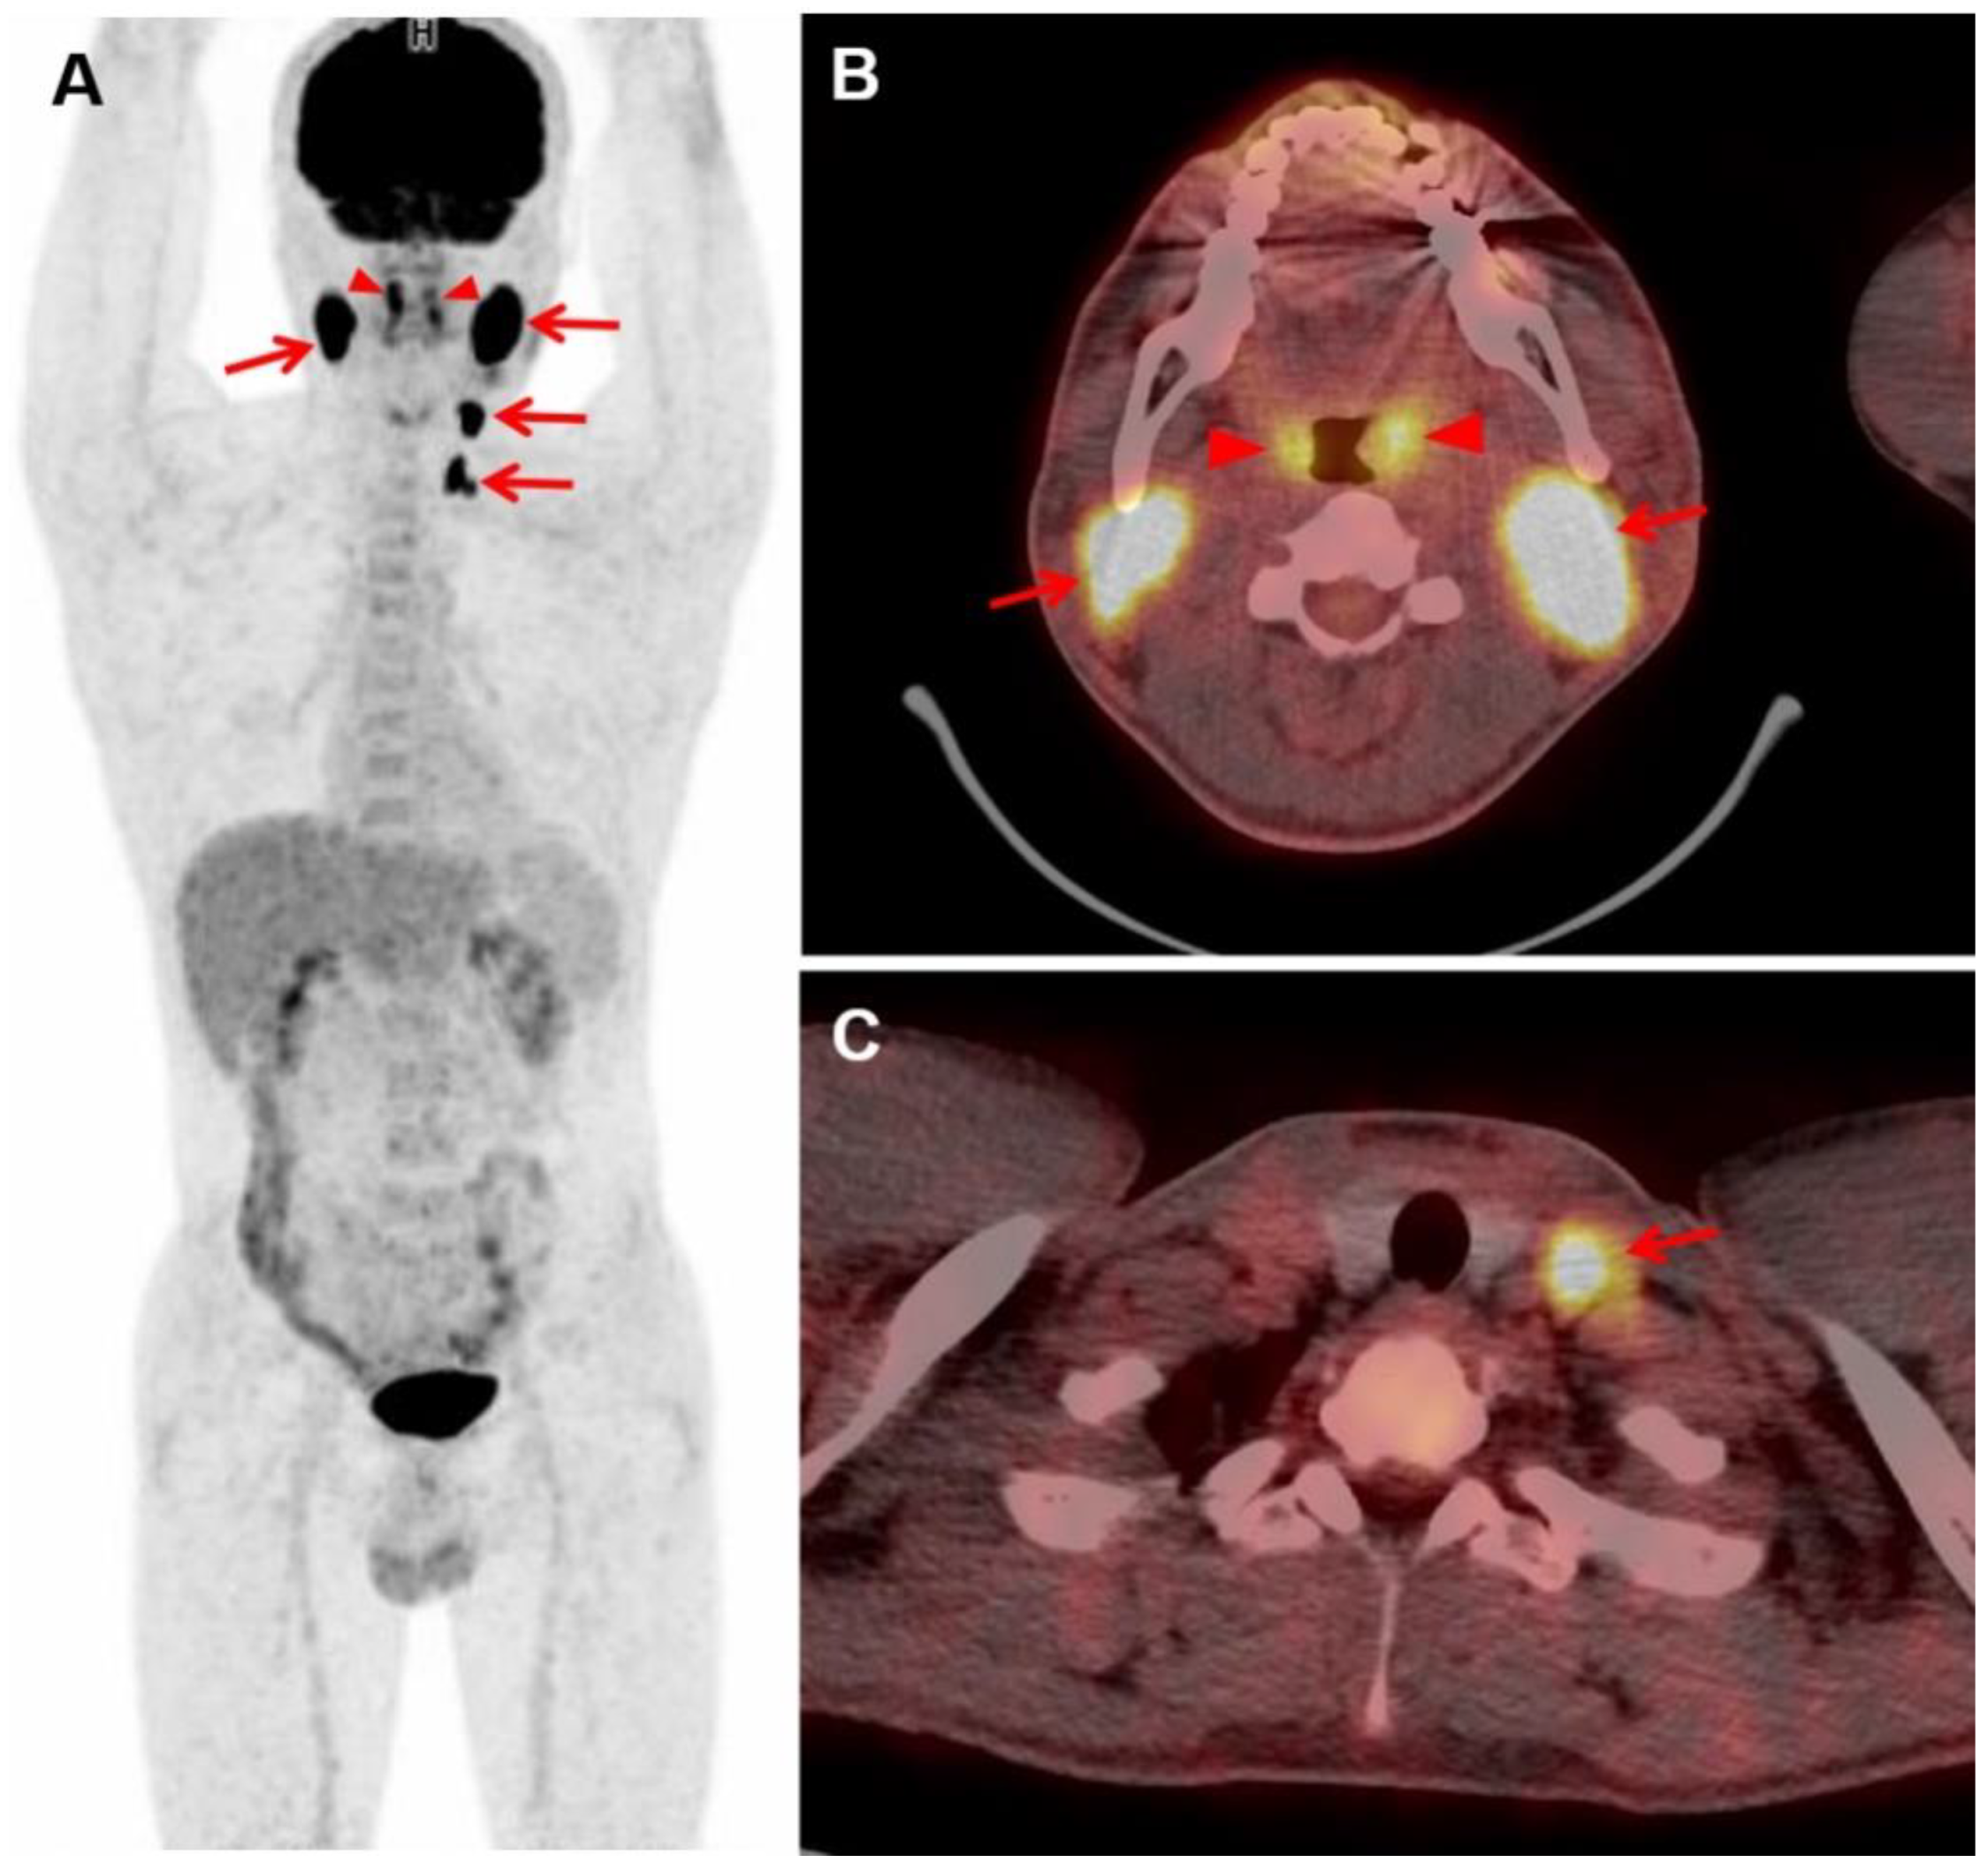

3.2. Visual Analysis of FDG PET/CT Images